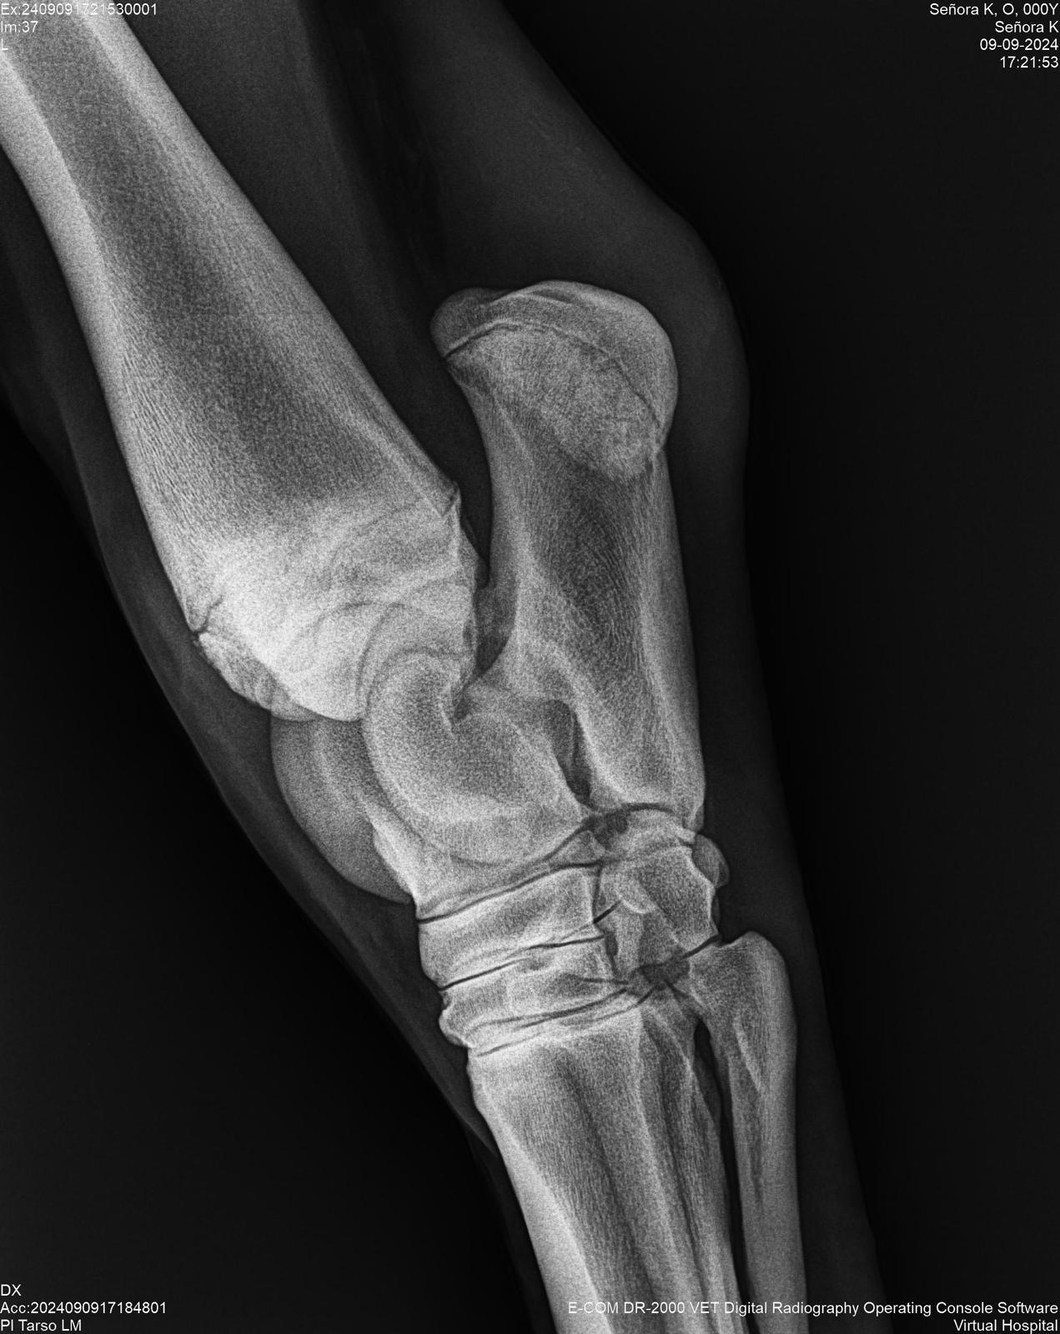

LOTE 44, SEÑORA K

Identificador: #291147-

Generacion 2022